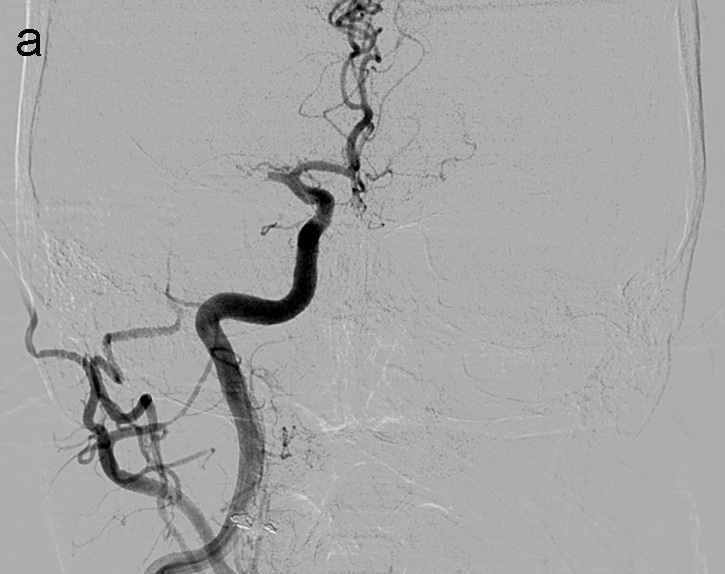

La técnica ADAPT consiste en usar el microcatéter y la microguía con el fin de facilitar la navegación del catéter de aspiración hasta aproximadamente 1-2 cm del trombo, momento en el que se retiran la microguía y el microcatéter y la llave en ‘Y’ avanzando el catéter de aspiración hasta que deja de refluír sangre por el ‘hub’. Tras esto se conecta la bomba de aspiración, se hincha el balón del FlowGate2 (imagen 2) con contraste diluido (50:50), se aspira con una jeringa de 50 cc través de éste último y se realiza el pase retirando el catéter aspiración.

Se realiza una serie a través del catéter balón que demuestra una recanalización parcial del segmento M1 proximal con apertura de arterias lenticuloestriadas y persistencia oclusión de segmento M1 distal de ACM derecha (imagen 3). Se decide cambiar de estrategia y usar la técnica SAVE con Catalyst 5, Trevo Pro 18, Asahi Chikai 0.014’’ y Catch 6 x 30 mm.